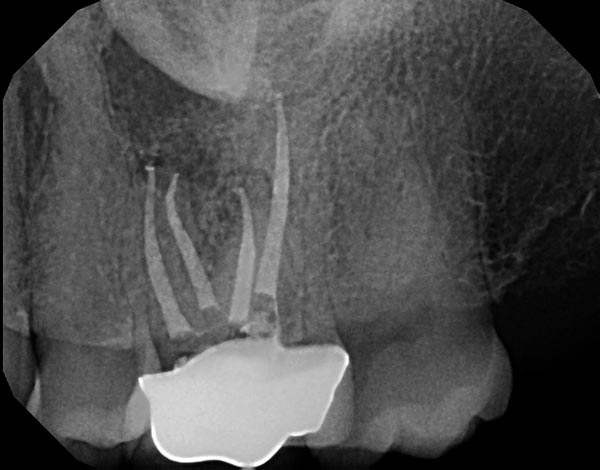

Fig. 2a: A distal angled preoperative image shows a well-defined radiolucency at the MB root apex and the previous root filling is off center, suggesting an untreated ML canal. Fig. 2b: An axial view of a CBCT clearly demonstrating the missed ML canal. Fig. 2c: Re-treatment was completed and the final shape of the canals was achieved using WaveOne Gold from Dentsply Sirona, a reciprocating, single file system that has a variable taper. Fig. 2d: At six-month recall, the tooth was asymptomatic and bone healing was complete as the PDL space and trabecular pattern were normal.

Fig. 2c

Fig. 2d